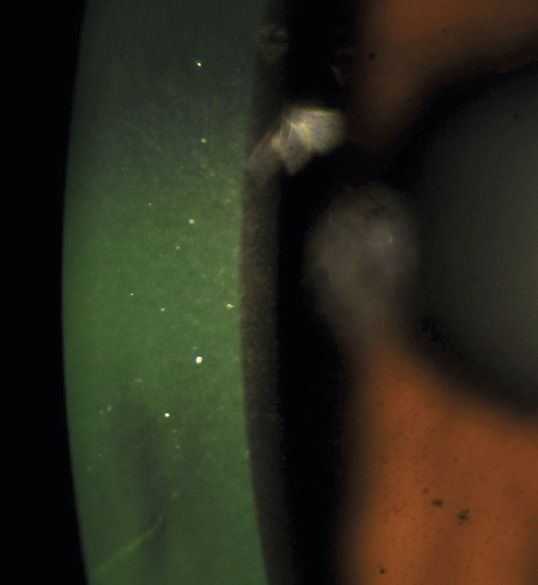

A 46-year-old African American male presents for glaucoma quarterly monitoring. Medical history is positive for hypertension controlled with 50 mg hydrochlorothiazide and reports no diagnosis of diabetes mellitus or known drug allergies. Ocular history is positive for progressive myopia bilaterally and pigment dispersion syndrome converting to pigmentary glaucoma right eye mild, left eye moderate with treatment initiated in September of 2016. The pigmentary glaucoma was treated with 0.005% latanoprost in both eyes every evening. There was positive family history of glaucoma (patient’s father). Best corrected visual acuity was measured at 20/25 in each eye. Pupillary assessment revealed a stable 1+ afferent pupillary defect in the left eye. Confrontation fields were full to finger count in the right eye and superonasal constriction in the left eye. Extraocular motilities were full with no restrictions or report of diplopia in both eyes. Slit lamp examination is remarkable for a Krukenberg spindle (Figure 4) bilaterally and a Zentmeyer line (Figure 5) in the left eye. Intraocular pressures at 3:30 pm via GAT measured 18 mmHg right eye, 23 mmHg left eye. Gonioscopy was performed and revealed open angles to ciliary body with a concave iris configuration and 4+ trabecular meshwork pigmentation (Figure 6) and the posterior corneal surface. There was no pigment attached to the anterior lens surface. The highest recorded intraocular pressures prior to treatment were 27 mmHg right eye & 35 mmHg left eye. CCT measured 554 microns in the right eye and 538 microns left eye. Optic nerve head assessment revealed bilateral intact neuroretinal rims with vertical elongation greater in the left eye than the right with inferior neuroretinal rim thinning in the left eye (Figure 7).

Bild 4: Fall 2 – Krukenberg-Spindel OU